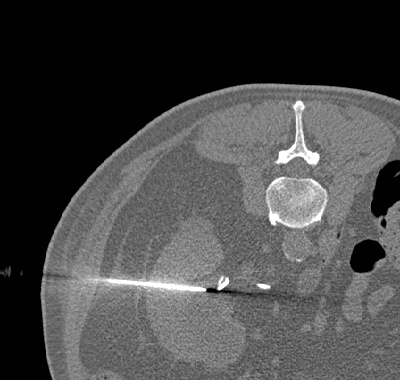

CT-gesteuerte perkutane Nephrostomaanlage bei einem einnierigen Patienten mit drohendem postrenalen Nierenversagen